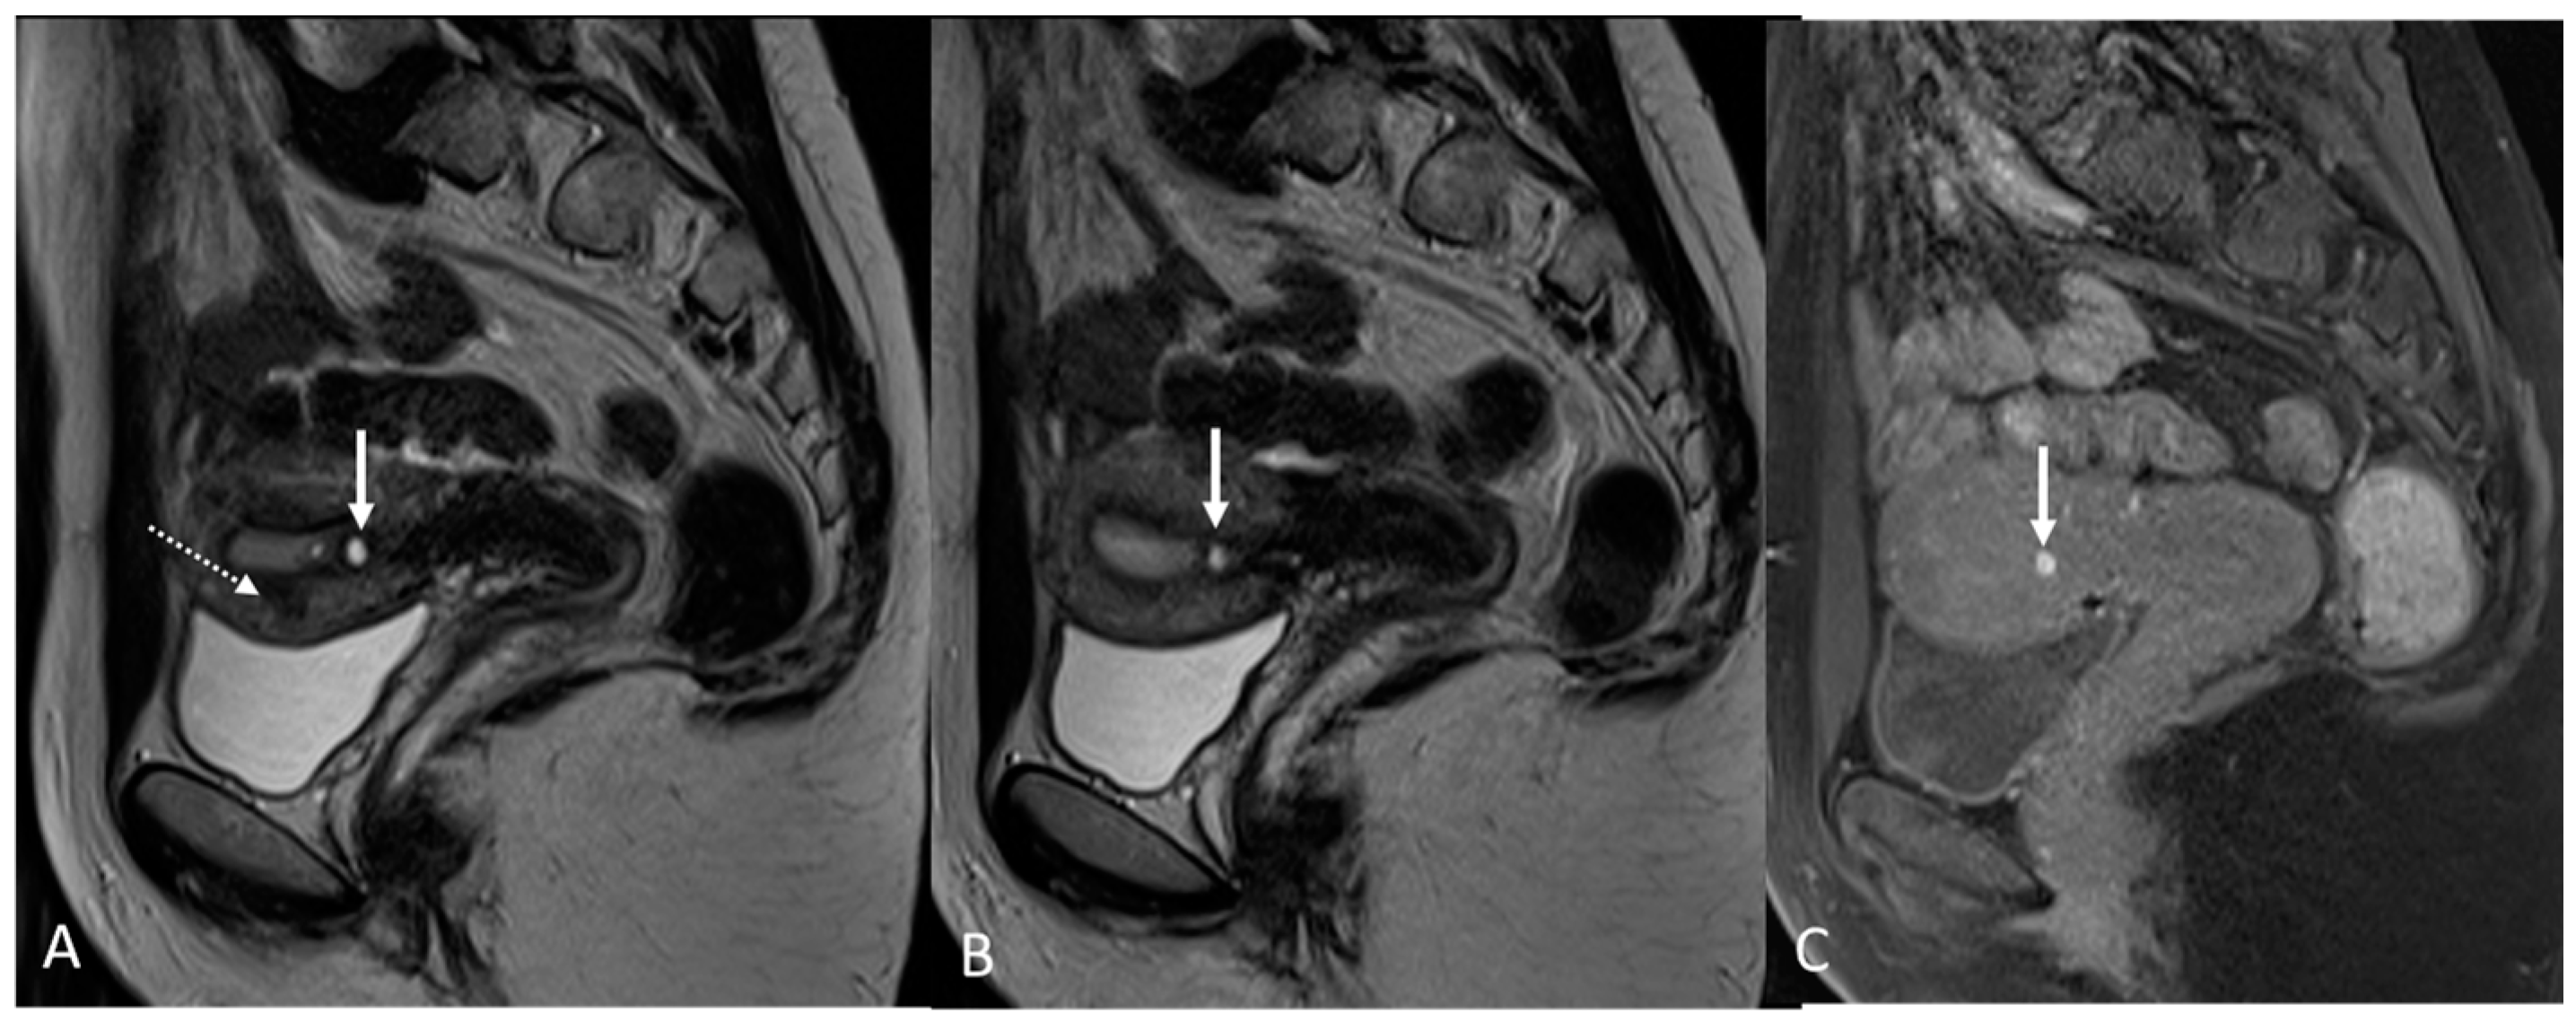

5. Adenomyosis

- -

- The parameter known as “ratiomax” corresponds to the ratio between JZmax and the total thickness of the myometrium, with a value exceeding 40% typically considered an acceptable diagnostic parameter [68];

- The parameter called “JZ differential” (JZdiff) measures the maximum and minimum thickness difference between the anterior and posterior uterine walls, where a value greater than 5 mm is indicative [68].

- Celli, V.; Dolciami, M.; Ninkova, R.; Ercolani, G.; Rizzo, S.; Porpora, M.G.; Catalano, C.; Manganaro, L. MRI and Adenomyosis: What Can Radiologists Evaluate? Int. J. Environ. Res. Public Health 2022, 19, 5840. [Google Scholar] [CrossRef]

- Chapron, C.; Vannuccini, S.; Santulli, P.; Abrão, M.S.; Carmona, F.; Fraser, I.S.; Gordts, S.; Guo, S.-W.; Just, P.-A.; Noël, J.-C.; et al. Diagnosing Adenomyosis: An Integrated Clinical and Imaging Approach. Hum. Reprod. Update 2020, 26, 392–411. [Google Scholar] [CrossRef]